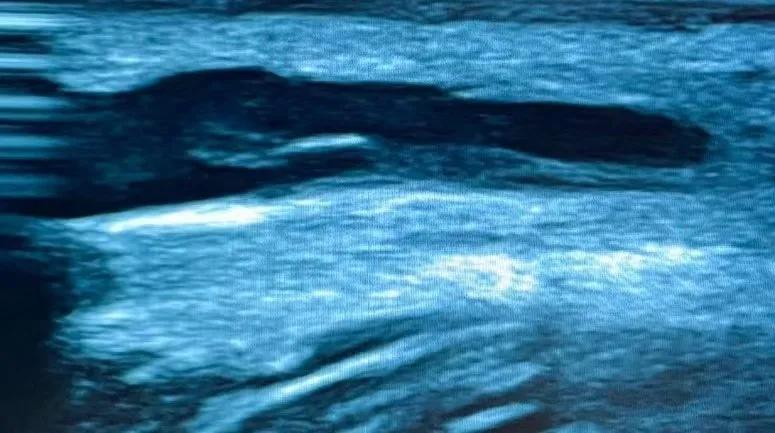

老渠多年糖尿病史,反复长期输液,术前评估发现其左上肢桡动脉尺动脉纤细,头静脉及肘正中静脉匮乏,头静脉前臂中段处有一处严重内膜损伤(见图1),桡动脉4.2mm,肱动脉分叉位于肘上,上臂贵要静脉束臂后2.8mm。右上臂头静脉条件略好,但肘上6cm处有一处内膜损伤,可能会影响内瘘成熟。经过详细的术前评估后,张东亮主任医师决定为患者行“左上肢桡动脉-贵要静脉人工动静脉内瘘血管转流”。这样既能绕开内膜损伤处,又可以为内瘘使用提供更多穿刺空间。

图1 超声提示静脉内膜损伤增生